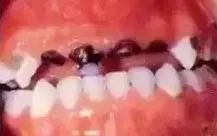

后全口牙遭殃

乳牙生病了,龋坏了长期不管,很有可能造成恒牙也毁容!